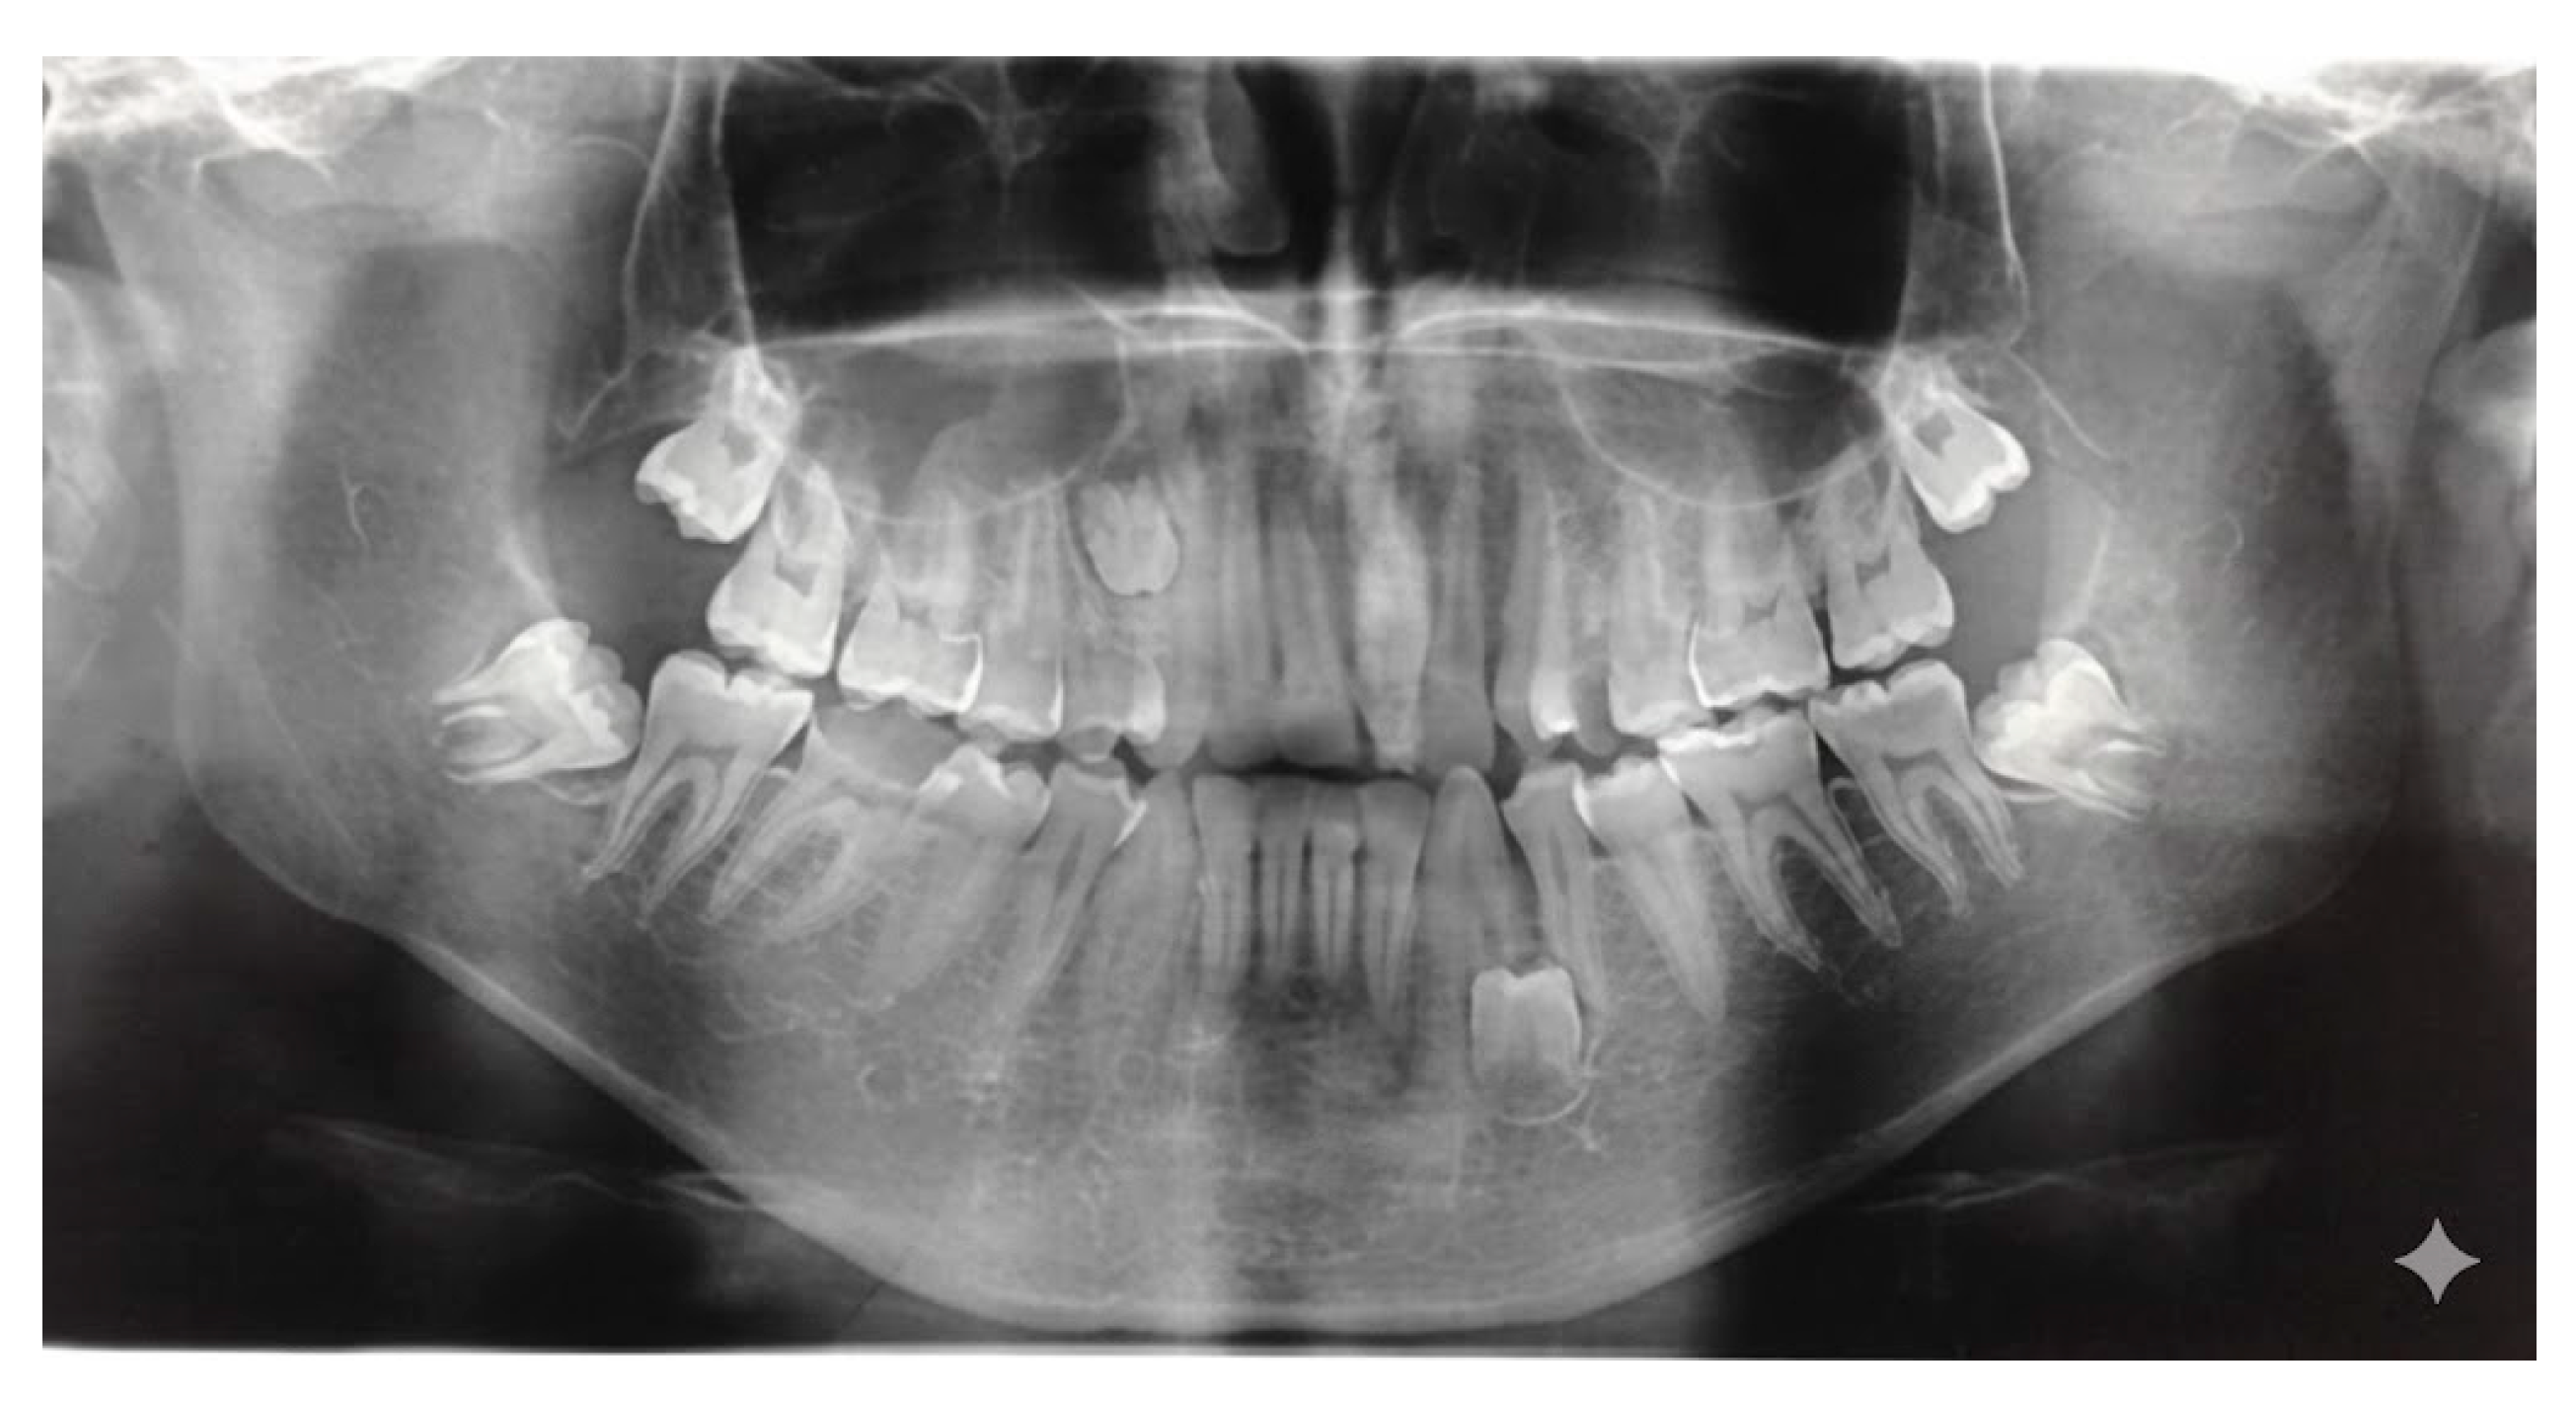

Cone-beam computed tomography (CBCT) addresses these limitations and has become a key diagnostic adjunct in contemporary diagnostic protocols [35]. CBCT allows high-resolution, three-dimensional imaging from a single scan, offering detailed visualization of supernumerary tooth morphology, spatial orientation (Figure 4), and proximity to vital structures such as the nasal floor, maxillary sinus, and mandibular canal [35,36].

Figure 4. Representative CBCT slice.